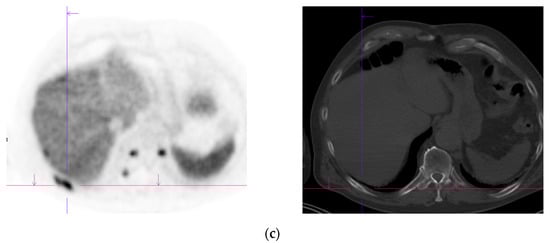

Figure 3.

Recurrent disease. 74 yr old M; radical prostatectomy 8 yrs prior; extensive para-aortic and upper pelvic lymph node involvement on CT; severe back pain; PSA 60. PSMA PET-CT: 68Ga-PSMA-216 MBq; uptake 48 min; BMI = 31.9; Wt 89 kg. (a,b): Coronal and sagittal images show bulky nodal disease with markedly increased uptake (SUV = 68.2) in abdomen and pelvis, hepatic metastases, multiple bony metastases in pelvis, lower limbs, sternum, ribs and vertebral column. (c): enlarged transaxial images of lower thorax/upper abdomen show tracer avid foci in segments 7 (SUV = 8.8), 4 (SUV = 8.7) of liver; X-hairs on lesion in right 10th rib, SUV = 14.6; CT on bone windows shows small region of sclerosis vs. extensive uptake on PET.